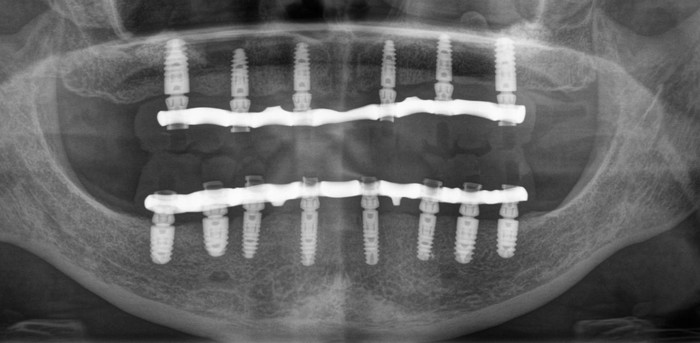

Тотальное протезирование на имплантатах

Здравствуйте, уважаемые друзья! Нередко ко мне на консультацию приходят пациенты, которым в силу тех или иных причин предписаны тотальная имплантация и протезирование зубов.

Ниже панорамный снимок зубов пациентки

На верхней челюсти были установлены шесть имплантатов и проведена операция по наращиванию костной ткани – синус-лифтинг (с обеих сторон). Через 2 недели установлены 8 имплантатов на нижней челюсти.

Панорамный снимок зубов